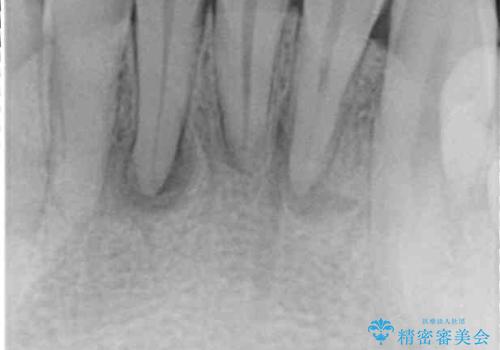

- 下の前歯がすり減って、痛みがあるとのことで来院された患者様です。

咬合力が強く、4本のうち3本の歯が失活しており、腫れや痛みが認められました。

3歯に根管治療を行い、その後4歯をオールセラミッククラウンにて補綴することとしました。

根管治療により腫れと痛みが引き、叢生の認められた歯列は補綴治療により改善され、清掃性が増しました。